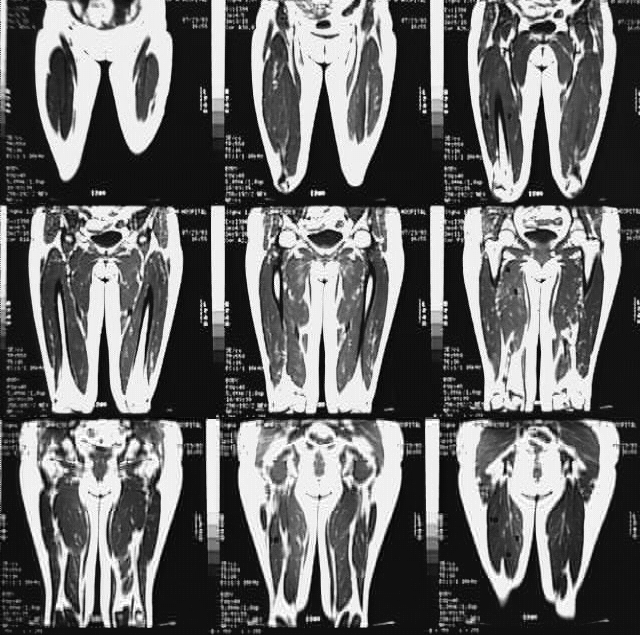

Radiology Images

Lower Limbs: Thigh MRI Coronal